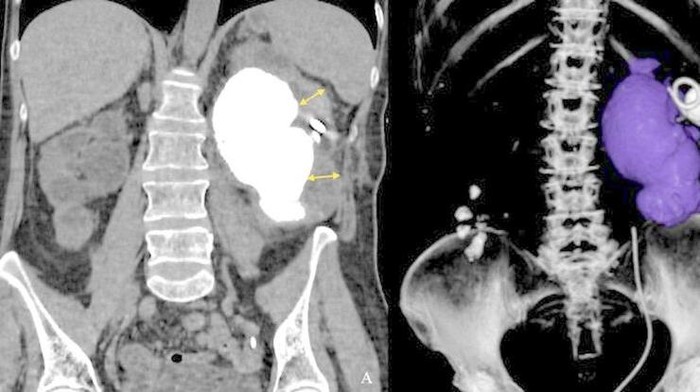

Dokter di Rusia berhasil mengangkat batu ginjal seberat 402 gram dari seorang pasien wanita berusia 55 tahun. (Foto: BMC Urology)

Pasien yang tidak disebutkan namanya itu awalnya datang ke rumah sakit dengan keluhan nyeri tumpul di daerah pinggang kiri. Sebenarnya pasien itu sudah didiagnosis batu ginjal sejak tahun 2004, tapi ia menolak menjalani intervensi bedah sampai gejalanya memburuk pada 2024. (Foto: BMC Urology)

Setelah dilakukan pemeriksaan, dokter menemukan batu ginjal kiri besar berukuran 13,6 cm x 8 cm x 6,8 cm. Dokter juga menemukan adanya beberapa batu kecil di ginjal kanan. (Foto: BMC Urology)